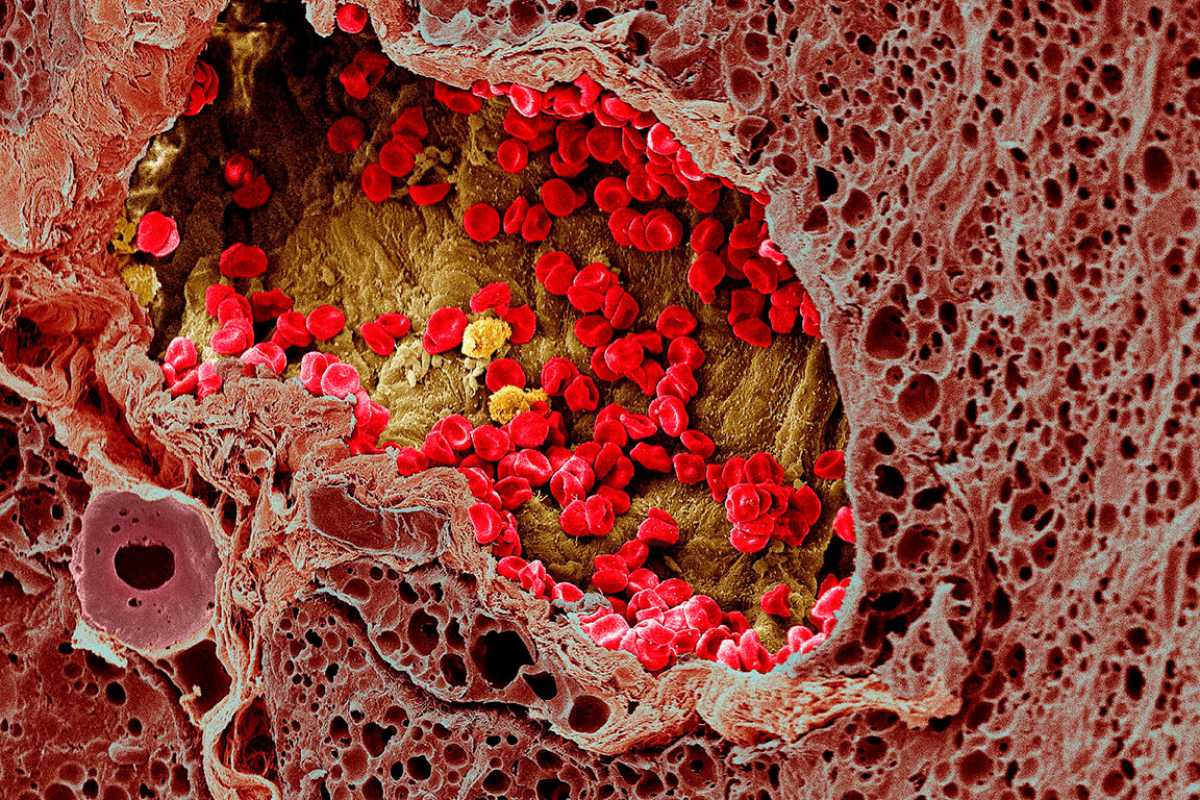

Раковая шишка – это заболевание, которое поражает кожу и слизистые оболочки. Она может возникнуть в различных частях тела и иметь различные внешние проявления. В данной статье мы представляем вам многочисленные фотографии раковых шишек, чтобы вы могли узнать, как они выглядят.

Раковые шишки могут возникать не только на лице, но и на других частях тела. На фотографиях вы можете увидеть примеры раковых шишек на шее, руках, ногах и туловище. Обратите внимание на различные формы и размеры раковых шишек, а также на их внешний вид.